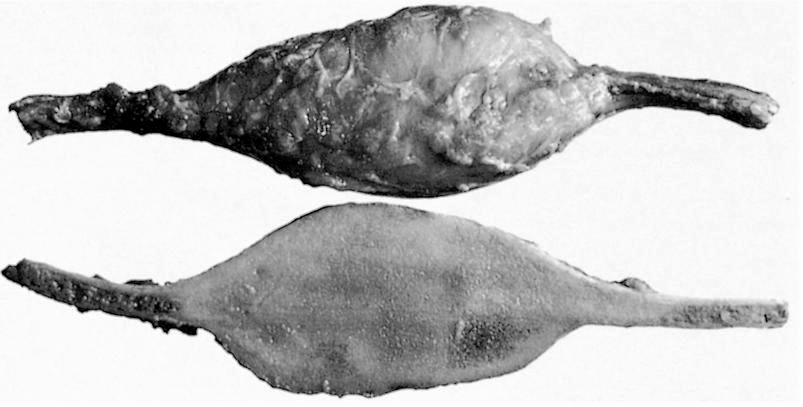

Gross description

- Well circumscribed lesion with a sclerotic rim centered within the cortex

- Cortex may be thinned as lesion expands

- Lesion itself may undergo aneurysmal bone cyst-like changes or cartilaginous metaplasia (Dorfman and Czerniak: Bone Tumors, 2nd Edition, 2015)

Gross images